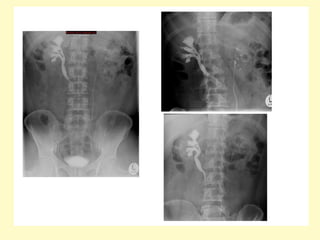

(a) Excretory urogram after 30 min shows severe dilatation of the right pelvocalyceal

system with cortical thinning and smooth obstruction of the right ureteropelvic

junction, (b) CTA with a maximum intensity projection technique demonstrates two

renal arteries originating from the aorta, an inferior aberrant artery (arrow) is crossing

over the ureteropelvic junction